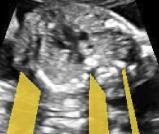

We propose a novel method based on convolutional neural networks (CNNs) to automatically estimate pixel-wise confidence maps of acoustic shadows in 2D US images. Our method learns an initial latent space of shadow regions from images consisting of multiple anatomies and with global image-level labels (“has shadow” and “shadow-free”), e.g. Fig. 1(a). The basic latent space is then estimated by learning from fewer images of a single anatomy (fetal brain) with coarse pixel-wise shadow annotations (approximately of the images with global image-level labels), e.g. Fig. 1(b). The resulting latent space is then refined by learning shadow intensity distributions using fetal brain images so that the latent space is suitable for confidence estimation of shadow regions. By using shadow intensity information, our method can detect more shadow regions than the coarse manual segmentation, especially relatively weak shadow regions.

We propose a shadow-seg module to extract generalized shadow features for a large range of shadow types in fetal US images under limited weak manual annotations. Since shadow regions have different shapes, various intensity distributions and uncertain edges, the pixel-wise annotation of shadow regions is time consuming and relies heavily on annotator’s experience (e.g. various annotations in Fig. 1(b)). This generally results in manual annotations of limited quantity and quality. Compared with pixel-wise shadow annotations, global image-level labels (“has shadow” and “shadow-free” in our case) are easier to obtain, and shadow images with global image-level labels can contain a larger variety of shadow types. Therefore, we use a shadow-seg module that combines unreliable pixel-wise annotations and global image-level labels as weak annotations.The proposed shadow-seg module contains two tasks, (1) shadow/shadow-free classification using image-level labels, and (2) shadow segmentation that uses few coarse pixel-wise manual annotations ( of the global image-level labels). Shadow features can be extracted during simple shadow/shadow-free classification and subsequently optimized for the more challenging shadow segmentation task. In our case, shadow features extracted by the classification network cover various shadow types in a range of anatomical structures. These shadow features become suitable for the shadow segmentation after being optimized by a shadow segmentation network.